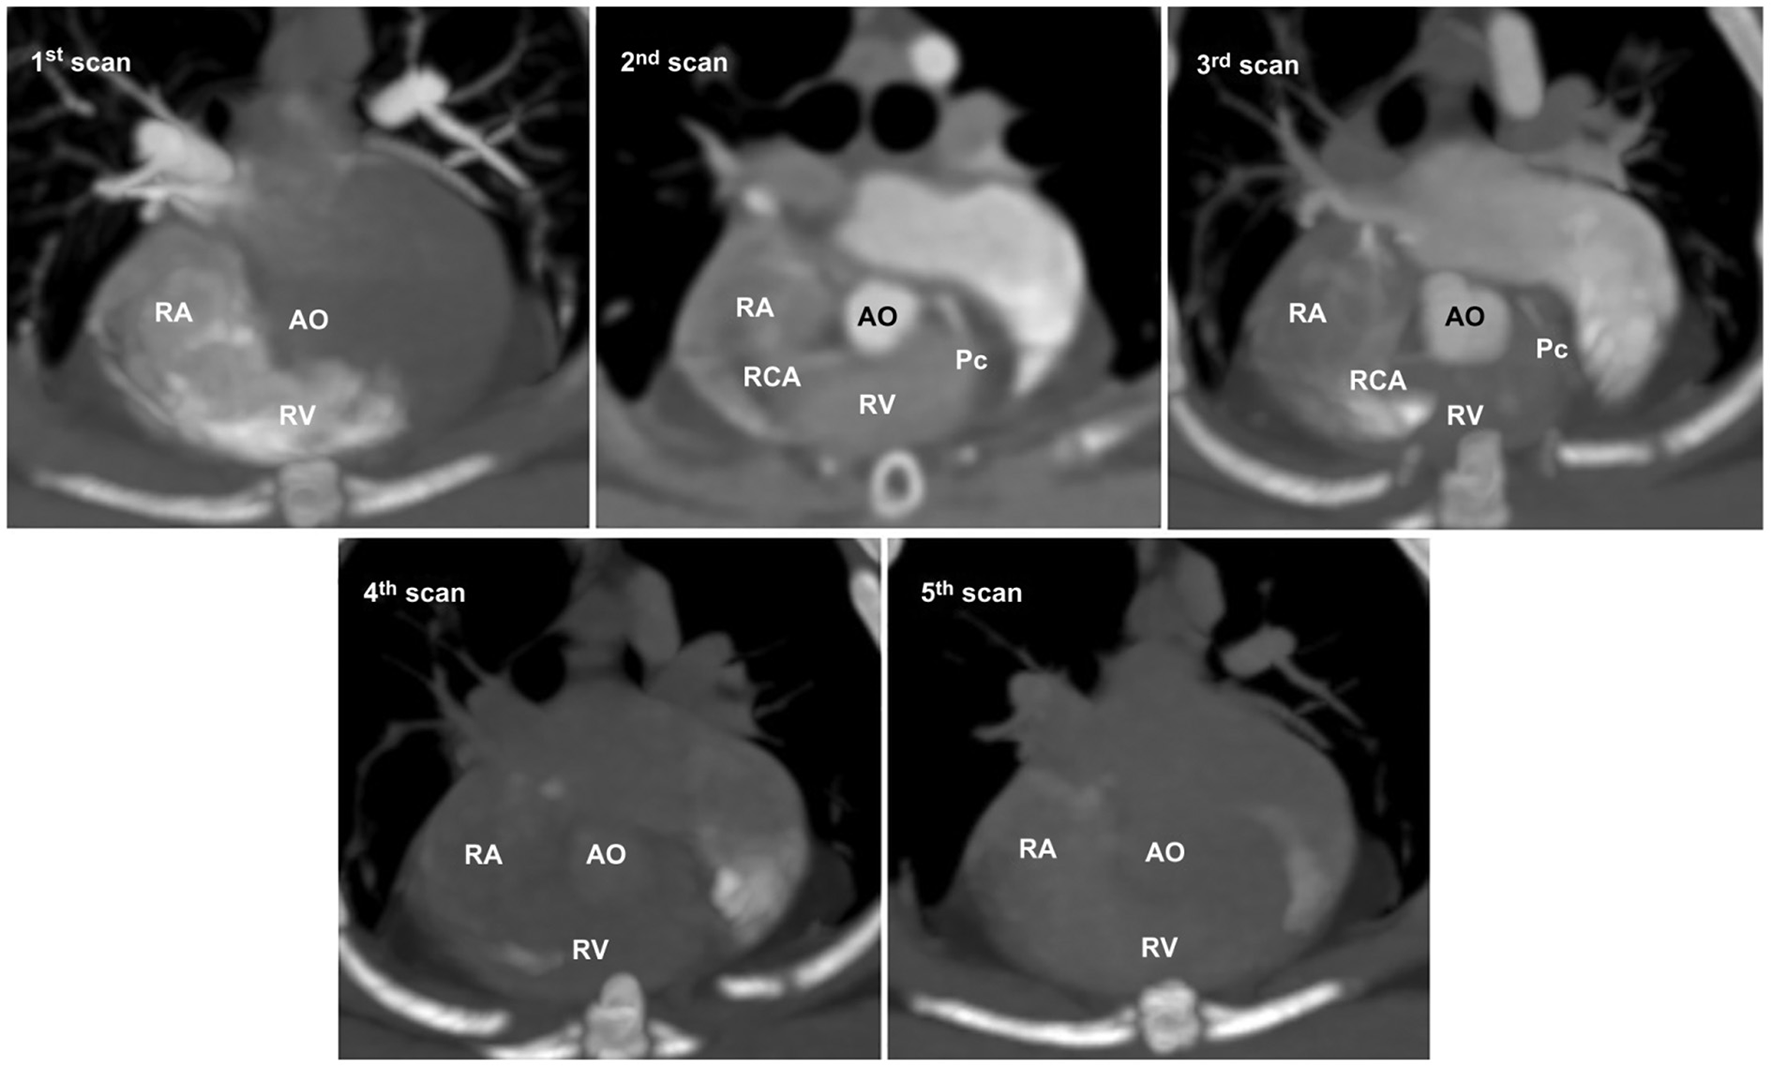

In non-ECG-gated images, the first scan exhibited no contrast enhancement in the left heart, which precluded the evaluation of the left heart and CAs in all cats (Figure 4). The second and third scans permitted visualization of the left and right main coronary stems at their origins but produced non-diagnostic images owing to blurring, streaking, and stair-stepping caused by cardiac motion artifacts, which obscured a detailed evaluation of the course of the CAs (Figure 4). The fourth and fifth scans did not provide suitable images owing to poor opacification of the left heart and CA resulting from wash-out of the contrast medium (Figure 4).

Figure 4

Five representative sequential non-electrocardiography (ECG)-gated multidetector computed tomographic (MDCT) images. In non-ECG-gated images, the first image shows no contrast enhancement in the left heart. The second and third images allow visualization of the left and right main coronary stems at the origin but produce non-diagnostic images for evaluating the detailed course of the coronary arteries owing to severe cardiac motion and blurring. The fourth and fifth images show poor opacification owing to the wash-out of the contrast medium. AO, aorta; Pc, paraconal interventricular branch; RA, right atrium; RCA, right coronary artery; RV, right ventricle.